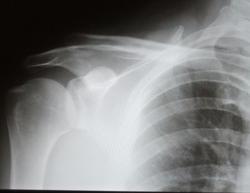

Описать как смещение акромиального конца ключицы кверху на ПОЛНУЮ ширину аромиального отостка ключицы и трактовать - как вывих. А в чем, собственно, сложность?

Никогда не забуду меткие лаконичные заключения М.И.Спузяка :"Верхний акромиальный вывих прав. ключицы". Чего еще мудрить?

Михаил Иванович вообще мастак на лаконизмы))))), а чего воду лить))). По мнению кафедры варианта два: либо описываешь картинку и в конце делаешь вывод о вывихе, либо сразу пишешь - "верхний акромиальный вывих правой ключицы" и всех делов)))